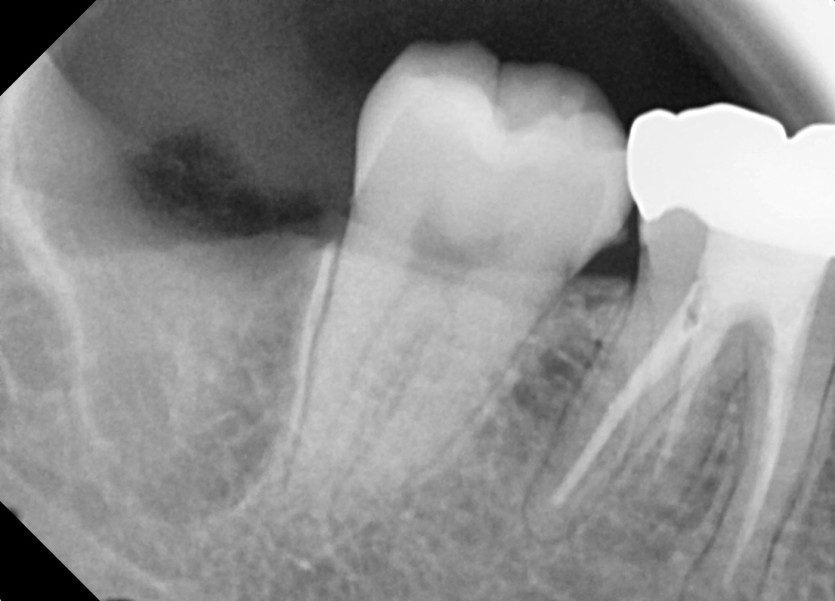

#48 사랑니 발치

구강외과 전문의가 당일 발치했습니다.